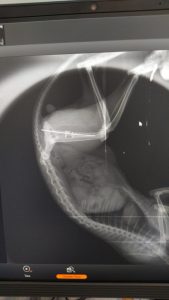

röngen2